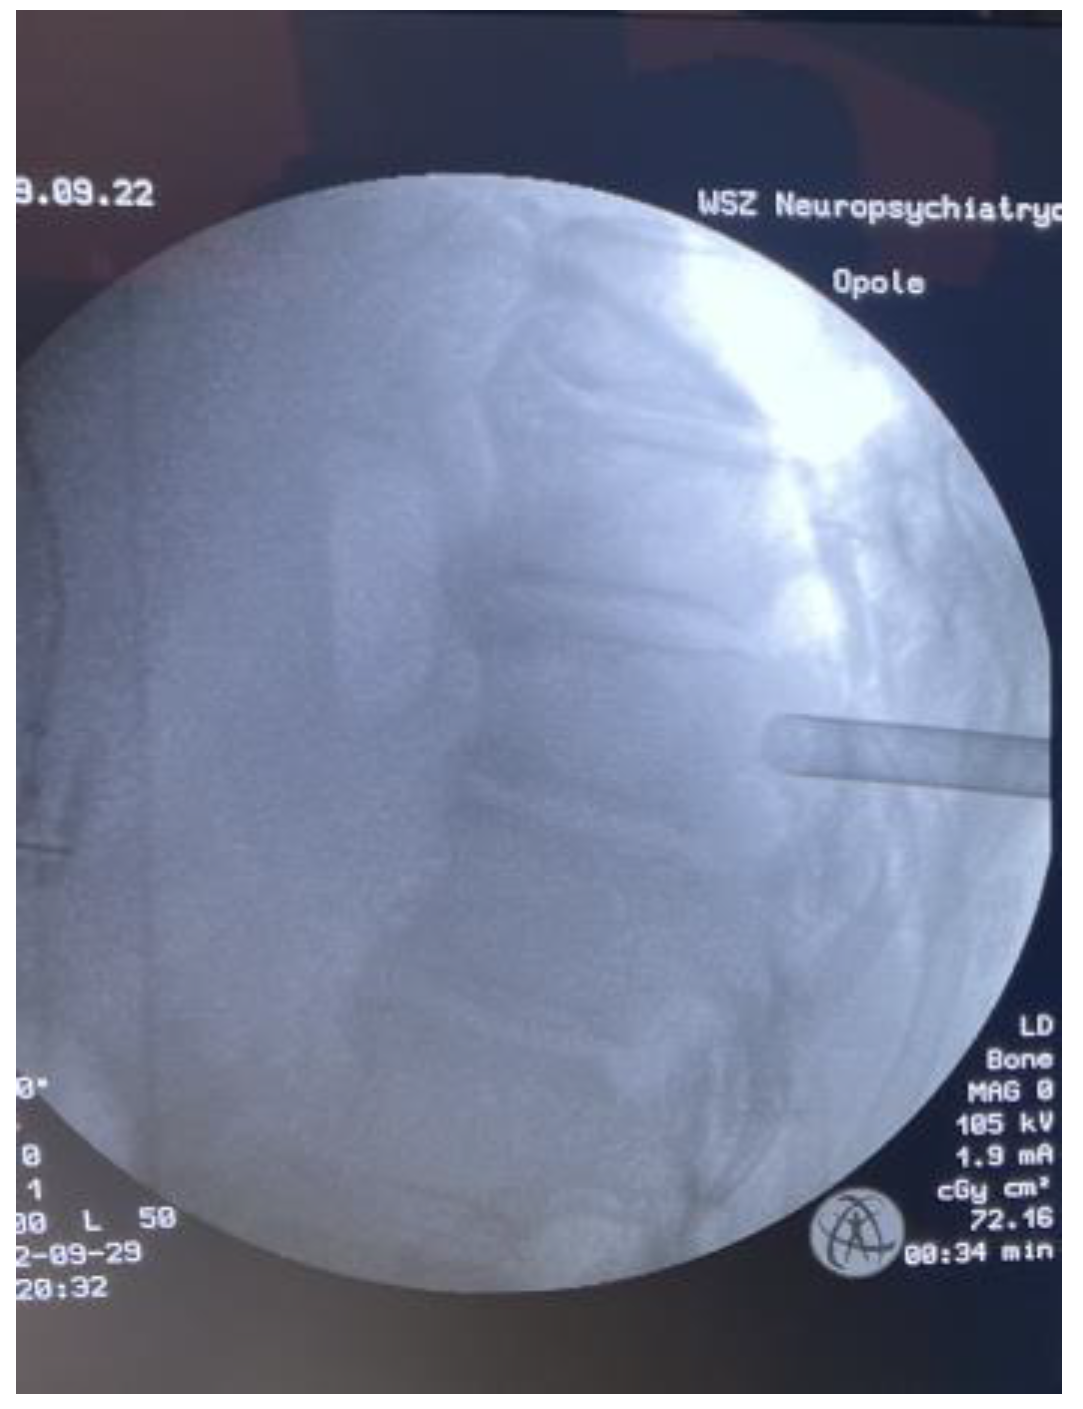

2. Materials and Methods

3. Results